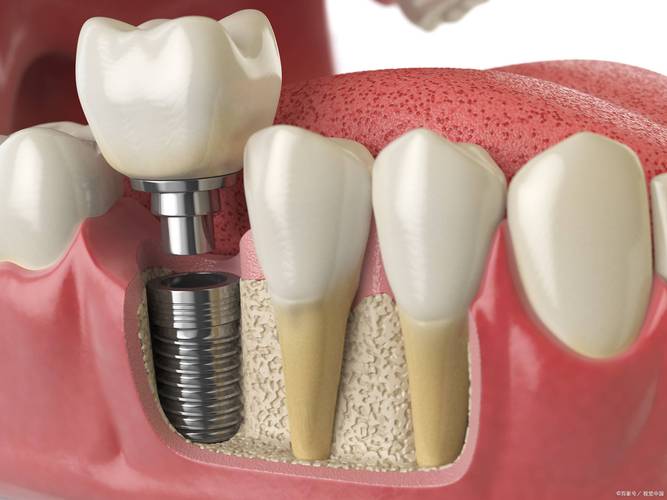

上颌第一磨牙,也就是我们常说的“上6”,是口腔中承担咀嚼功能最重要的牙齿之一,位于上颌骨后部,通常有3-4个牙根,负责研磨食物,对维持咬合关系和面部形态至关重要,但由于位置靠后、受力大,加上清洁难度较高,上6也是龋坏、牙周炎等疾病的高发区域,一旦严重损坏或缺失,不仅会影响咀嚼效率,还可能导致邻牙倾斜、对颌牙伸长等问题,进而引发颞下颌关节紊乱等连锁反应,种植牙作为目前公认的牙齿缺失最佳修复方式,因其功能、美观及长期稳定性优势,成为上6缺失后的首选方案,本文将详细解析上6种植牙的适应症、种植流程、材料选择、风险护理及费用等关键信息,帮助全面了解这一修复技术。

- 备洞与植入:根据术前设计的方向和深度,用专用钻针逐级备洞(由细到粗),避免产热损伤骨组织;将种植体(类似螺钉状)旋入牙槽骨,确保初期稳定性(种植体周围骨面有接触,无松动)。